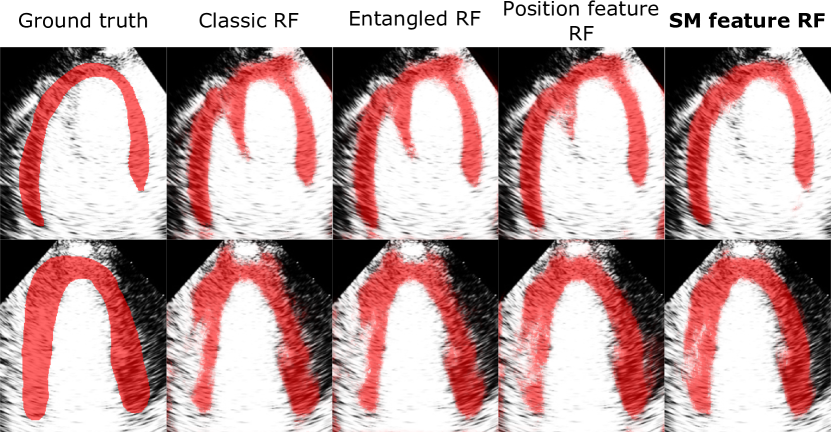

Figure 4: Visual comparison of the RF probability maps obtained by different RF variants.

We study the effect of SM feature on RF segmentation by comparing it with the classic RF that uses simple intensity features [36] as well as RF that uses other contextual features such as the entanglement features [28] and position features [17]. We use the sub-images extracted from the manual bounding boxes BBManual to train and test all the RFs in this section.

Fig. 5 compares the probability maps generated by RFs using different features. Our SM feature produces smoother and more coherent probability map. Other RFs often misclassify low intensity structure in the LV cavity as myocardium (row 1) and the high intensity region in the myocardium as background (row 2). RF with SM feature can overcome these problems by imposing a global shape constraint.

Fig. 5 shows the segmentation performance of different RFs at different tree depths. Our SM feature RF outperforms the other RFs at all tree depths. This is because the SM feature captures the explicit geometry of the myocardium to guide the segmentation. A binary test of the SM feature in the split node partitions the image space using meaningful myocardial shape based on the shape model. Position feature [17] also learns the myocardial shape implicitly but its binary test partitions the image space using simple straight line which is less effective. To learn complex shape like the myocardium, many more position feature tests are needed compared to SM feature tests which learn the myocardial shape directly. This causes SM feature to be the more discriminative feature at lower levels of the tree, leading to better results than other RFs especially at lower tree depths.